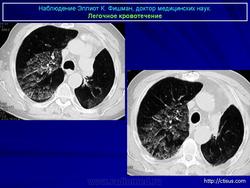

Лёгочное кровотечение. Fri, 23/09/2011 - 23:36 #1 Катенёв Валенти... Offline Last seen: 7 years 5 months ago Joined: 22.03.2008 - 22:15 Posts: 54876 Продолжение.Приложения: Sat, 02/06/2012 - 01:19 #2 Катенёв Валенти... Offline Last seen: 7 years 5 months ago Joined: 22.03.2008 - 22:15 Posts: 54876 Лёгочная геморрагия.Приложения: Sun, 03/06/2012 - 21:48 #3 Nikolas Offline Last seen: 1 month 4 weeks ago Joined: 21.12.2010 - 20:37 Posts: 4560 уважаемый Валентин Львович, что Вы почти всегда даете литературную справку во время какой-либо дискуссии. Ваши иллюстрации на мое клиническое наблюдение, как всегда, своевременны и актуальны. Спасибо. С уважением Nik. Sun, 03/06/2012 - 21:41 #4 Катенёв Валенти... Offline Last seen: 7 years 5 months ago Joined: 22.03.2008 - 22:15 Posts: 54876 Я постараюсь в ближайшее время пополнить этот набор. Wed, 10/09/2014 - 13:20 #5 Катенёв Валенти... Offline Last seen: 7 years 5 months ago Joined: 22.03.2008 - 22:15 Posts: 54876 Продолжение.Приложения:

Продолжение.